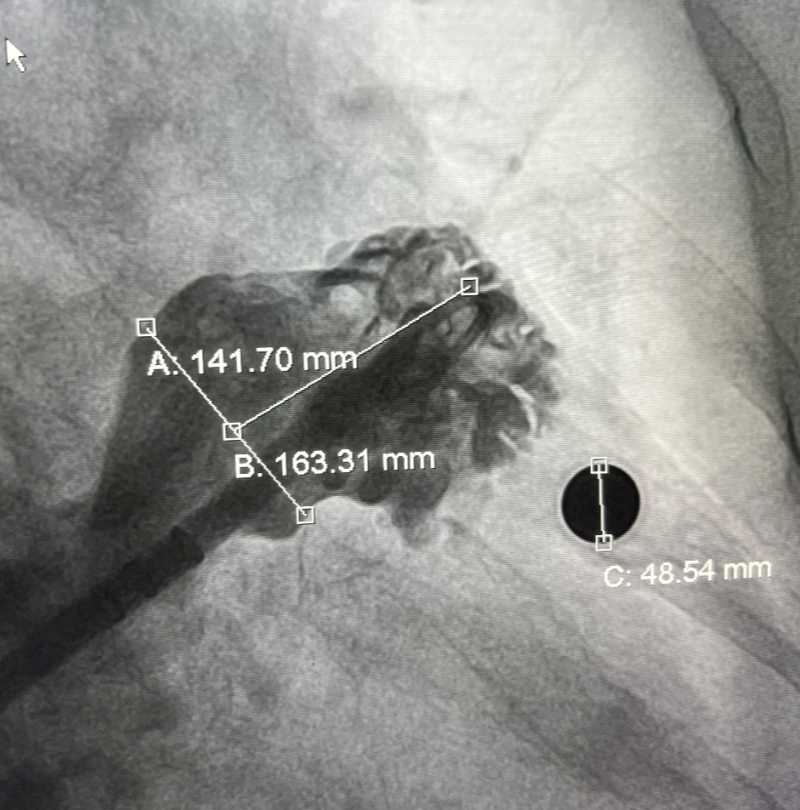

經過完善的術前CT和全面的Truplan軟件術前分析準備。在介入室的全面配合下完成該患者的術前準備工作,謝桂庭進行房間隔穿刺,精準定位穿刺位點。行左心耳造影,造影結果顯示開口28mm左右,深度32mm左右。結合術前Truplan結果以及術中DSA測量結果,選用WATCHMAN 33mm封堵器進行封堵。